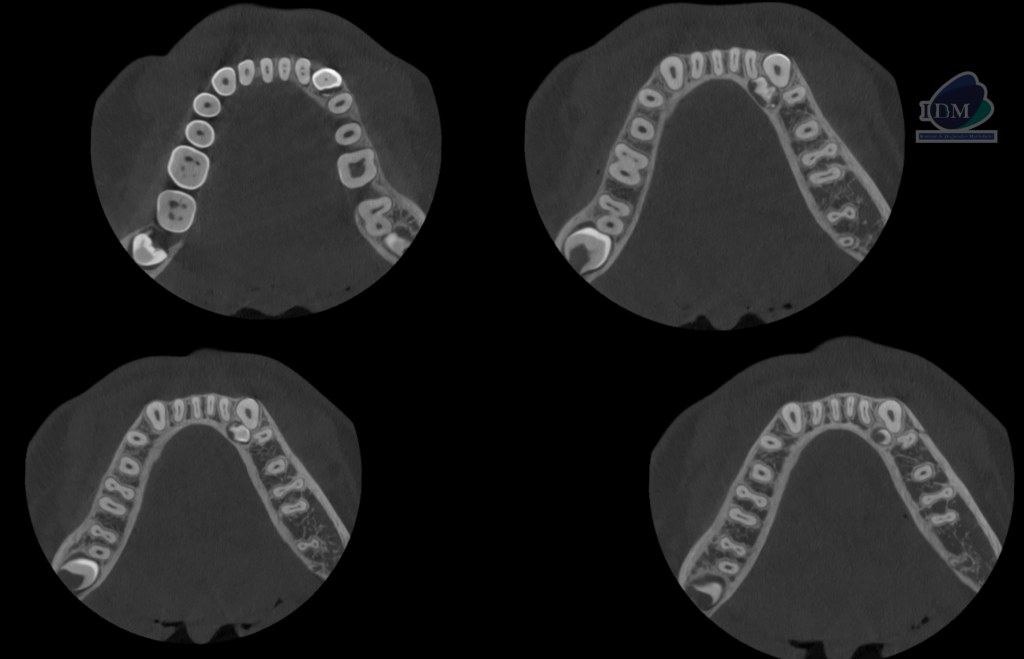

A la evaluación de la tomografía volumétrica (cone beam) en los cortes axiales (Figura 2) y transaxiales (Figura 3) se observa múltiples dentículos por lingual de la pieza 33, rodeado por un halo isodenso, de dimensiones 8,30 mm x 8,70 mm x 5,40 mm aproximadamente, que ocasiona el adelgazamiento de la tabla ósea lingual y la pérdida de la lámina dura lingual de la pieza 32.

CORTES AXIALES